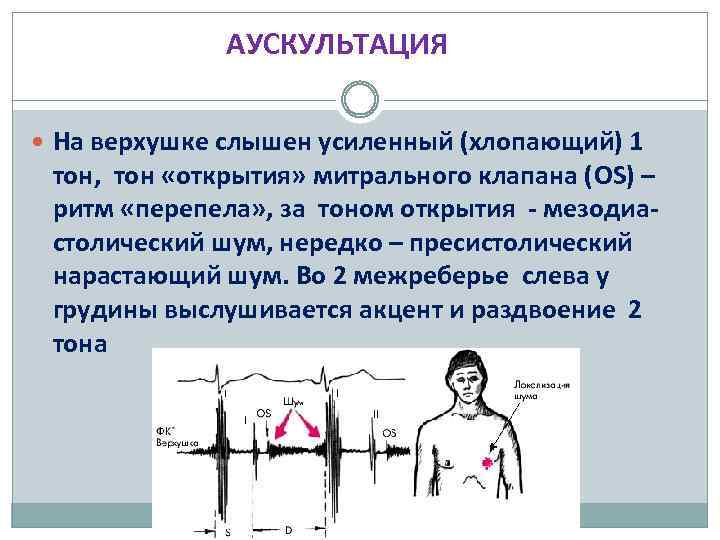

АУСКУЛЬТАЦИЯ На верхушке слышен усиленный (хлопающий) 1 тон, тон «открытия» митрального клапана (OS) – ритм «перепела» , за тоном открытия - мезодиастолический шум, нередко – пресистолический нарастающий шум. Во 2 межреберье слева у грудины выслушивается акцент и раздвоение 2 тона